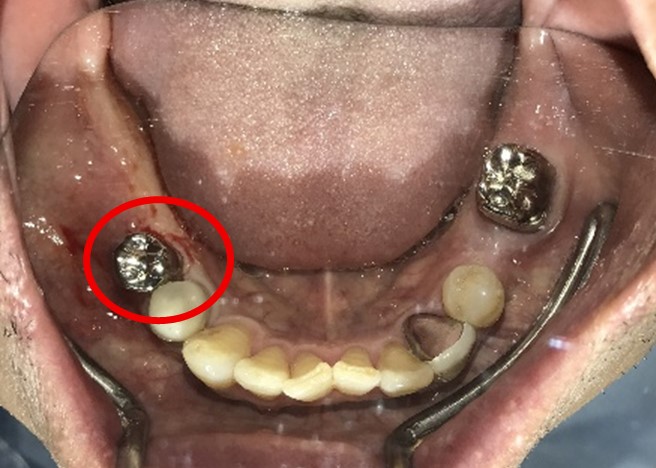

男性 Nさん 70代 (インプラント)

主訴

右下奥の歯が、グラグラして噛むと痛い。

治療内容

歯根の周りの骨が全く無い状態でしたので、保存することができず抜歯しました。3本歯がないところに2本インプラントを埋入しました。

所感

抜歯後、歯がなくなったところを補う方法には、部分入れ歯とインプラントがあります。この症例の場合、右下以外ほとんど歯が残っていますので、もし部分入れ歯にした場合、入れ歯のところで他のところと同じ感覚で噛むことができないので、慣れることが大変です。また部分入れ歯の支えになっている歯に負担がかかりますので、今後さらに歯を失う可能性が大きくなります。インプラントは、自分の歯と同じ感覚で噛むことができ、単独で植立していますので他の歯に負担がかかることがありませんので、更に歯を失うことを防ぎます。

インプラント2本:¥363,000×2本=¥726,000(税込)

ポンティック1本:¥115,500(税込)

合計:¥841,500(税込)

Before

※赤丸を抜歯しました。

After